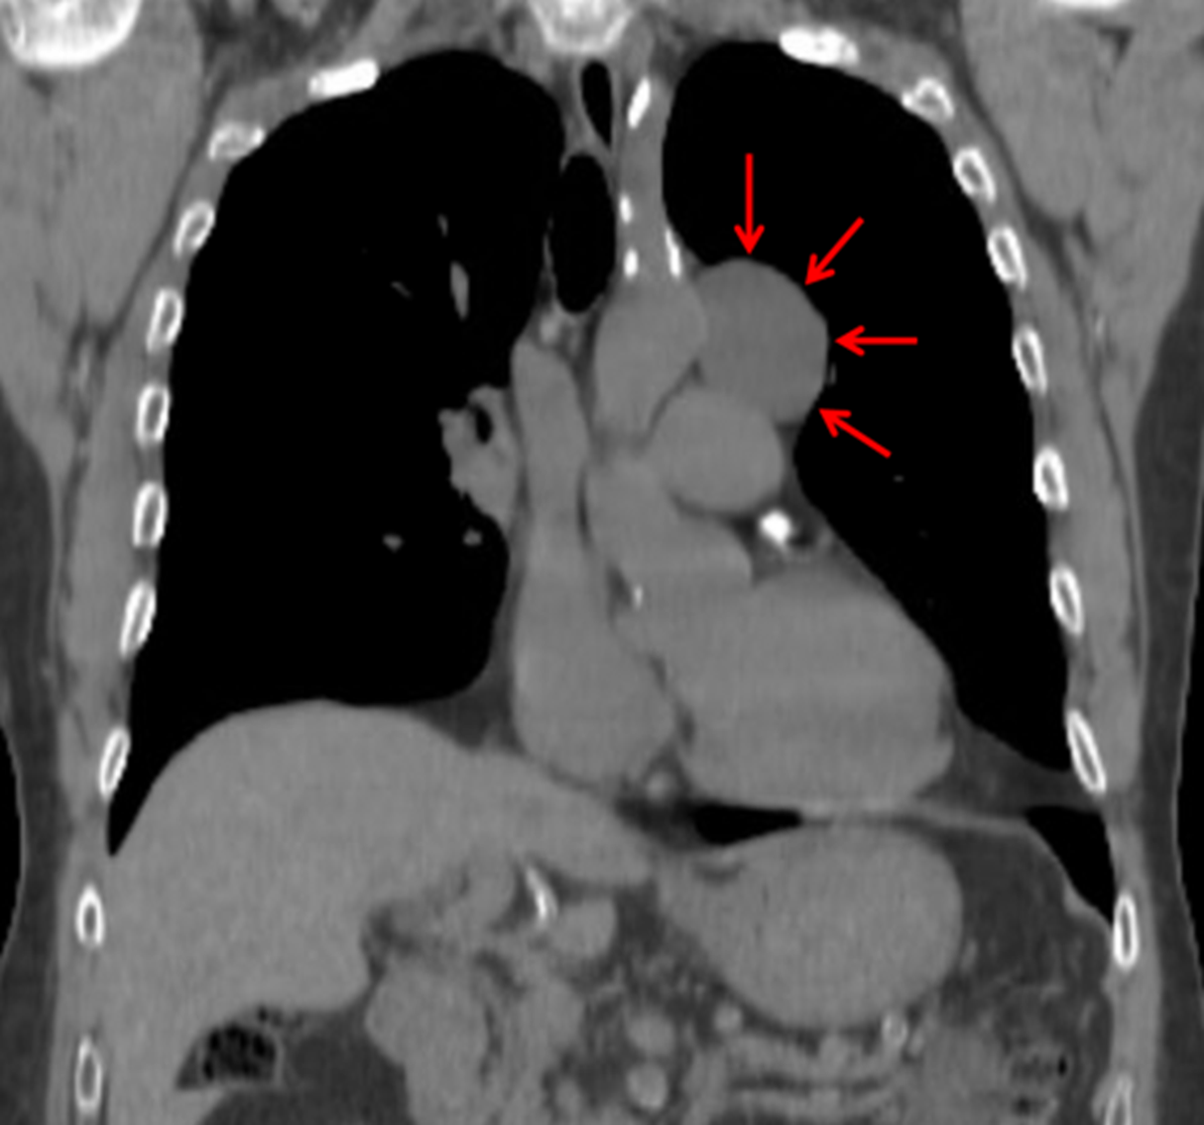

Middle mediastinal mass (duplication cyst)

• This case turned out to be a benign duplication cyst (see CT below)

CT demonstrated a middle mediastinal mass most consistent with a benign duplication cyst (red arrows).